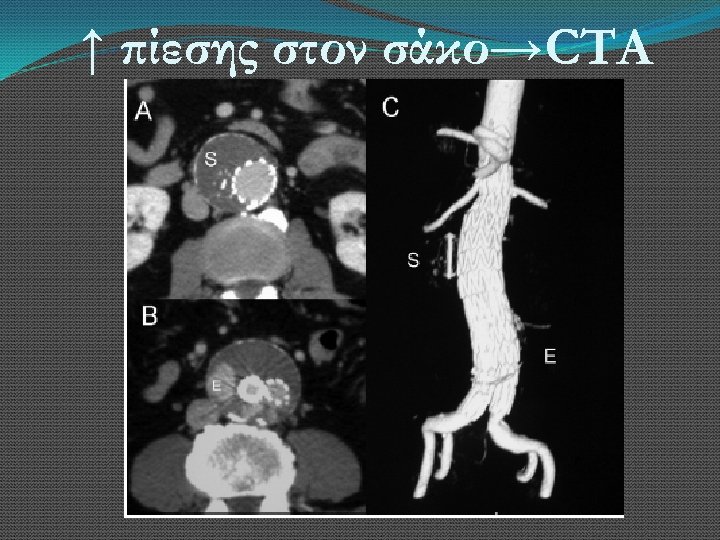

↑ πίεσης στον σάκο→CTA